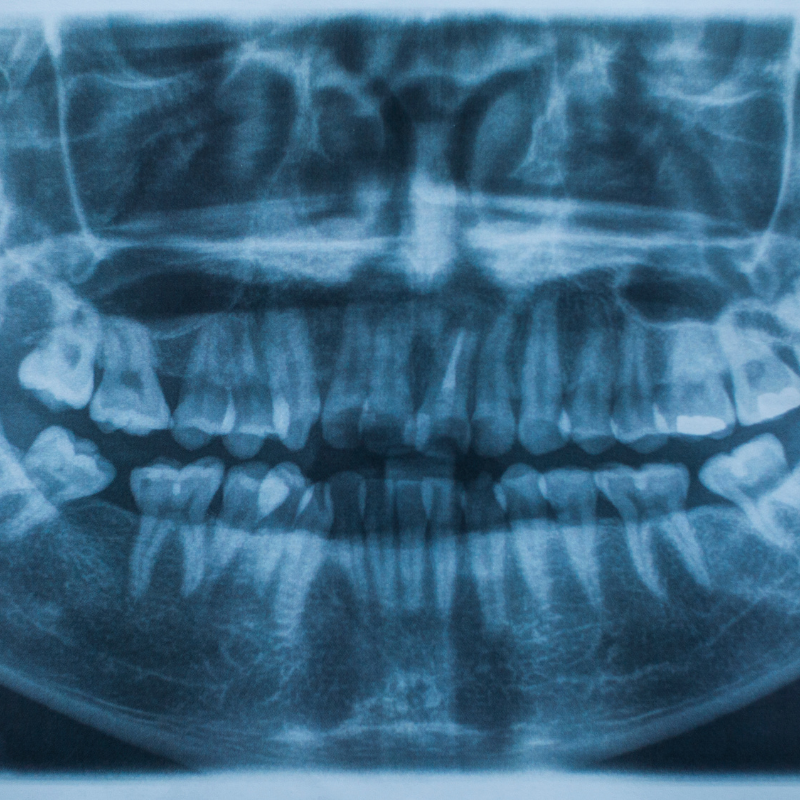

Η πανοραμική ακτινογραφία δοντιών προσφέρει μια ολοκληρωμένη εικόνα της στοματικής κοιλότητας. Το οδοντιατρικό κέντρο μας διαθέτει υπερσύγχρονο εξοπλισμό για ψηφιακές πανοραμικές ακτινογραφίες στην Αθήνα, παρέχοντας πλήρη απεικόνιση σε μία μόνο λήψη. Η τεχνολογία αυτή είναι ιδανική για την αξιολόγηση της συνολικής οδοντικής κατάστασης, τον εντοπισμό έγκλειστων δοντιών και τον προεγχειρητικό σχεδιασμό.

Οι ενδοστοματικές ακτινογραφίες αποτελούν το θεμέλιο της καθημερινής διαγνωστικής πρακτικής. Η ενδοστοματική ακτινογραφία επιτρέπει τη λεπτομερή εξέταση μεμονωμένων δοντιών και των περιακρορριζικών ιστών, αποκαλύπτοντας τερηδόνες, περιοδοντικά προβλήματα και ενδοδοντικές παθήσεις. Η υψηλή ευκρίνεια των ψηφιακών αισθητήρων μας εξασφαλίζει την ακριβή διάγνωση ακόμη και των πιο δυσδιάκριτων παθολογικών καταστάσεων.